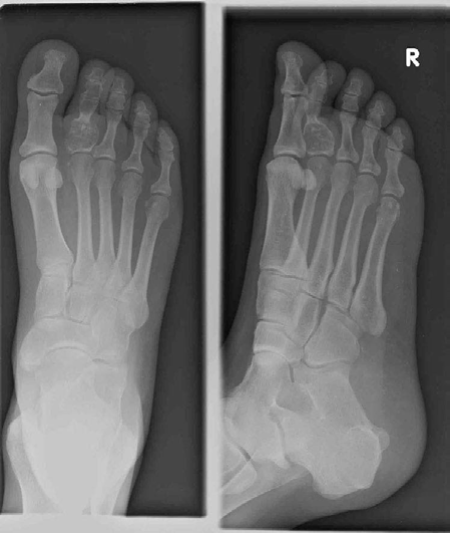

Lower limb Trauma Structured oral examination question 1 A 35-year-old motorcyclist came off his bike yester-…